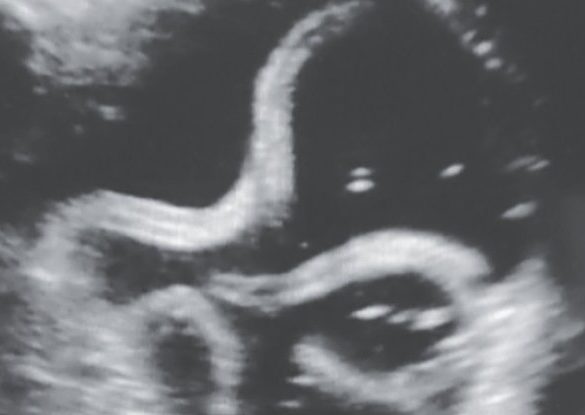

An ultrasound of a man’s stomach captured some unwelcome inhabitants – a tangle of parasitic roundworms squirming around, according to...